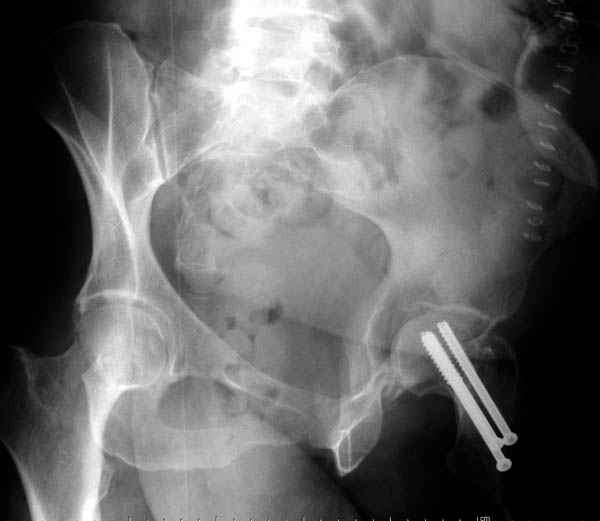

Вложение не в текстовом формате было извлечено…

Имя     : 6 fem neck CRM.jpg

Тип     : image/jpeg

Размер  : 24442 байтов

На снимке ацетабулума редко встречающийся очень низкий перелом,

наверное, трудно было репозицию через один доступ? Перелом как бы

замкнулся в квадрилатеральной поврехности.